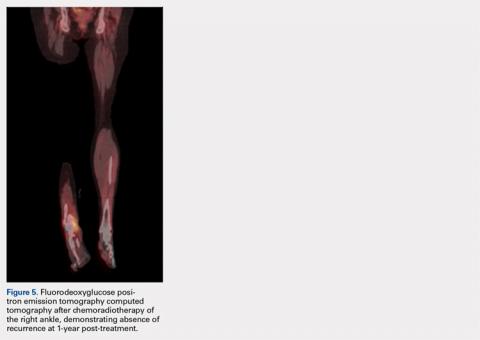

The patient was placed on her second cycle of chemoradiotherapy and again showed complete remission. At over 1-year follow-up, the patient’s wound had completely healed, and FDG PET-CT of the extremity was negative for ENKTL recurrence (Figure 5). At present, the patient’s medical oncologists recommend a stem cell transplant as the patient exhibited 2 positive responses to chemoradiotherapy.DISCUSSION

ENKTL is an uncommon form of lymphoma and is exceedingly rare in Caucasian females.1-3 Although the patient’s primary occurrence was in the nasal cavity, recurrence in the foot and ankle must still be described.7,8 To our knowledge, this article is one of the first published cases of a patient who developed a rare-recurrence ENKTL about the foot and ankle. Occurrence in extremities is extremely rare that the staging protocol does not include FDG PET-CT of these areas. The patient’s “negative” scans led many providers to neglect the symptoms in her right ankle until the lesion had ulcerated through the skin. If one would have relied on imaging reports and outside records alone, the diagnosis would have been delayed longer or missed all together. This case illustrates the importance of a thorough medical history and personal review of imaging studies, and how a systematic approach can produce the correct diagnosis for any unknown lesion. Furthermore, this case may prompt oncologists to consider obtaining whole-body FDG PET-CT when evaluating for recurrence in patients.